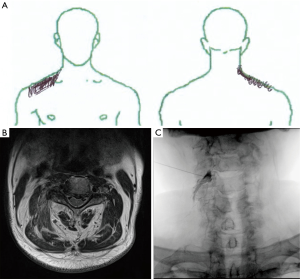

A 70-year-old-man visited the department of physical medicine and rehabilitation at a university hospital because of dull pain in his right upper trapezius muscle area (Figure 1A) for 1 month. Two weeks before, at a local pain clinic, the patient had been diagnosed with myofascial pain syndrome (MPS) in the right upper trapezius muscle and treated with a trigger-point injection (TPI) of lidocaine. However, there was no pain reduction after TPI. The numeric rating scale score was 6 out of 10. Physical examination revealed mild tenderness in the right upper trapezius muscle. Hyperalgesia was present at the right C4 dermatome without motor weakness in the right upper extremity. The Spurling test (right cervical lateral flexion with axial loading) increased the patient’s pain in the right upper trapezius muscle area. Deep tendon reflexes were normal in all four limbs and plantar responses were down bilaterally. Hyperalgesia in the right C4 dermatome suggested that the patient’s pain might have resulted from cervical radiculopathy. To evaluate cervical radiculopathy, we performed cervical magnetic resonance imaging (MRI), which revealed foraminal stenosis at the right C3–4 level (Figure 1B).

We conducted diagnostic fluoroscopy-guided right C4 selective nerve root block with 0.5 mL of 1% lidocaine, and the patient showed a positive response with complete transient pain resolution. Therefore, it was confirmed that the patient’s pain was the result of right C4 radiculopathy due to right C3–4 foraminal stenosis. To treat C4 radicular pain, we performed selective nerve root injection (SNRI) with 4 mg of dexamethasone mixed with 0.25 mL of 0.125% bupivacaine and 1.25 mL of normal saline at the right C4 nerve root (Figure 1C). Thirty minutes after SNRI, the patient’s pain in the right upper trapezius muscle area had completely resolved. At the 1- and 3-month follow-ups, the patient reported no pain.